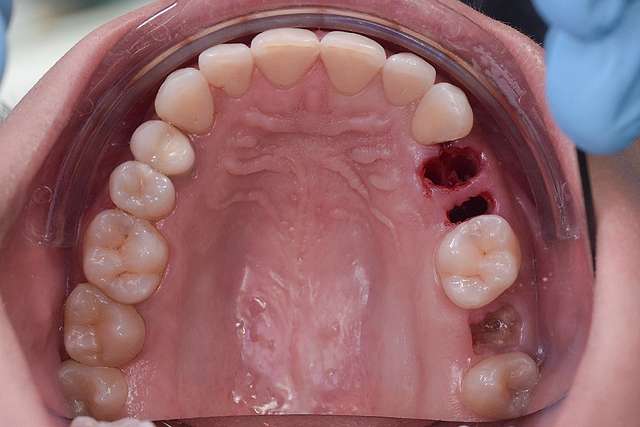

Implanturile dentare sunt tratamente indicate pentru dinti care nu mai sunt recuperabili. Implanturile au la baza lor principiul osteointegrarii, altfel spus, implantul se integreaza in os. Pentru o perioada lunga de timp, acesta a fost principalul obiectiv la nivel de industrie. Implantul sa fie integrat, sa fie plasat in functie de os. Astazi stim deja ca osteointegrarea este extrem de predictibilă si ne focusam pe alte elemente cheie care fac diferenta in calitate la un dinte restaurat cu implant dentar.

Chirurgia ghidata, ne faciliteaza o pozitie ideal pre-planificata, care nu tine cont doar de os, ci si de o pozitie optima in relatie cu viitorul dinte.Chirurgia ghidata înseamnă o precizie crescuta, care inseamna siguranta mai mare, timp operator mai scazut, si trauma mai mica. De asemenea focusul in acest tip de interventii a migrat spre reconstructia tesuturilor, care e pe termen lung are un impact mult mai mare atat estetic cat si biologic, inserarea implantului in sine fiind trivializata de folosirea ghidului chirurgical. Cazul de fata este un exemplu al acestui tip de abordare.